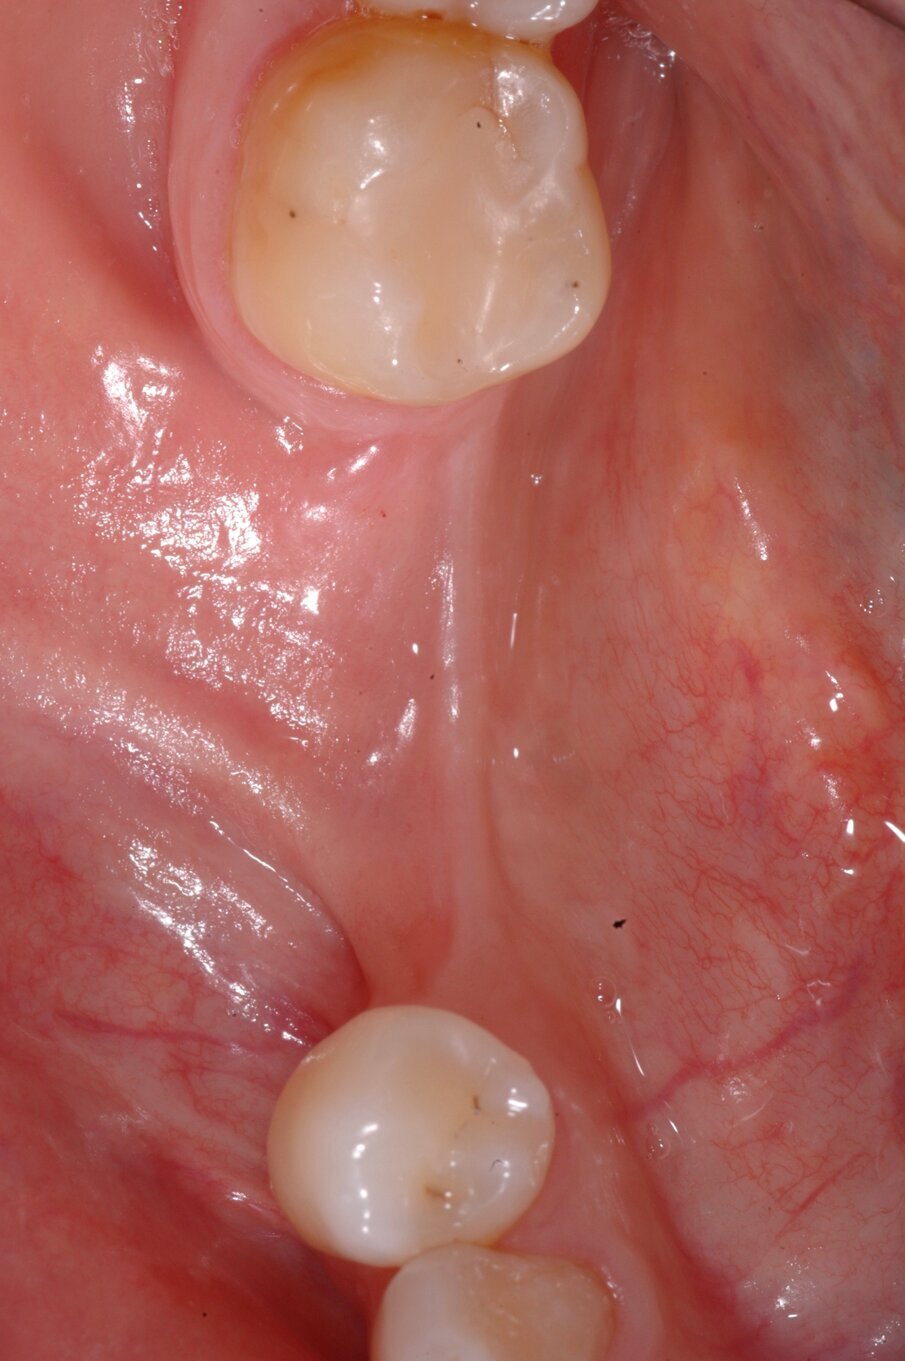

Nella rx si vedono i due impianti con le viti di guarigione ad integrazione avvenuta. In figura 16 si nota l’ottimo aspetto dei tessuti peri-implantari con una adeguata quantità e qualità di gengiva cheratinizzata e le susseguenti corone in metallo ceramica successivamente cementate su due perni moncone in titanio fresati in laboratorio. Nelle foto successive si possono evidenziare le differenze dalla situazione iniziale (Fig. 17) a quella finale, in questo caso una foto di follow up a 48 mesi dalla finalizzazione del caso (Fig. 18). La rx a quattro anni dalla finalizzazione protesica evidenzia una situazione di perfetta stabilità, una cresta ossea ben mineralizzata ed un livello osseo inalterato dal momento della consegna del manufatto protesico definitivo (Fig. 19).